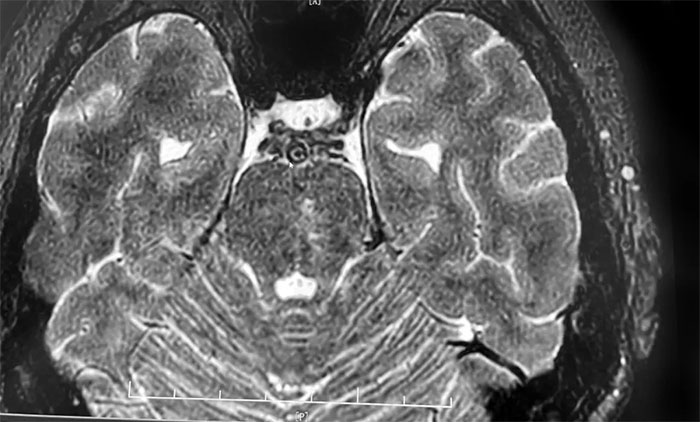

頭顱MRI+SWI+DTI提示腦干梗塞,雙側(cè)橋臂變性;雙側(cè)放射冠區(qū)、額頂葉散在腔梗、缺血灶;讋(dòng)脈HRMR平掃+增強(qiáng)提示基底動(dòng)脈管壁增厚伴重度狹窄。頭顱CTP顯示,右側(cè)頂枕顳葉局部腦組織灌注較對(duì)側(cè)稍減低。DSA提示基底動(dòng)脈中段重度狹窄。

▲ 腦干梗塞